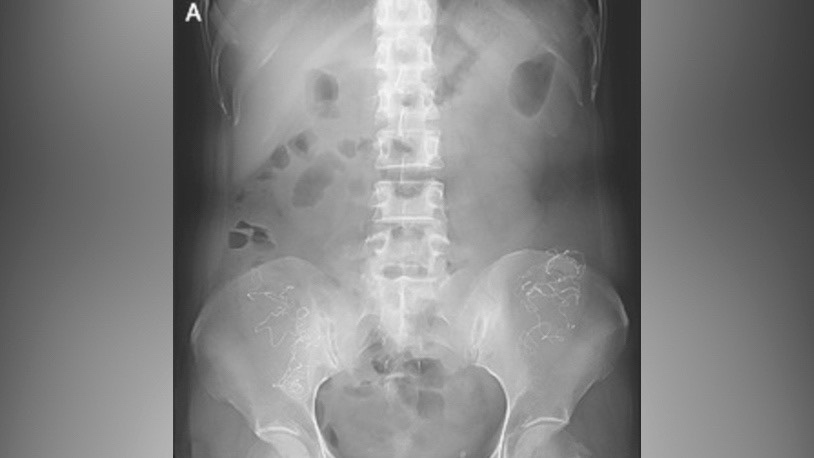

Это оказался кусок хирургической марли, забытый врачами во время операции много лет назад! Организм, пытаясь защититься, буквально "обернул" инородный предмет тканями, создав капсулу. Это состояние позже получило название госсипибома.

Самое поразительное – женщина прожила с этим почти 20 лет! Без современной диагностики, без понимания причины, с постоянной, необъяснимой болезнью внутри. После удаления марли её состояние резко улучшилось.